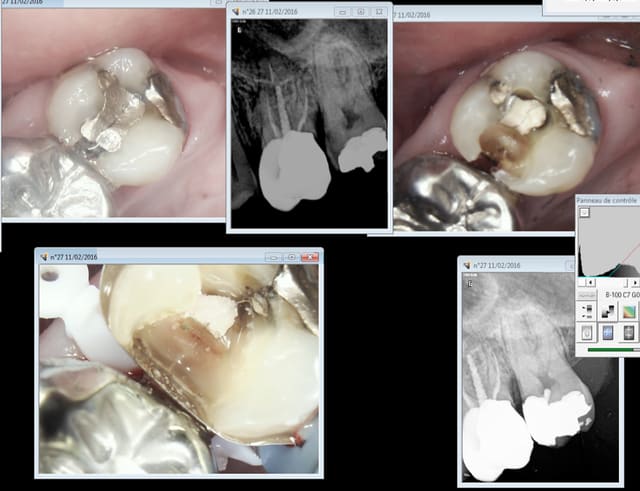

Capture_d_e_cran_2016-02-11_17.46.19_e8mhuc.png

Capture_d_e_cran_2016-02-11_09.03.34_uvuqiy.png

Capture_d_e_cran_2016-02-11_09.08.00_xkuqil.png